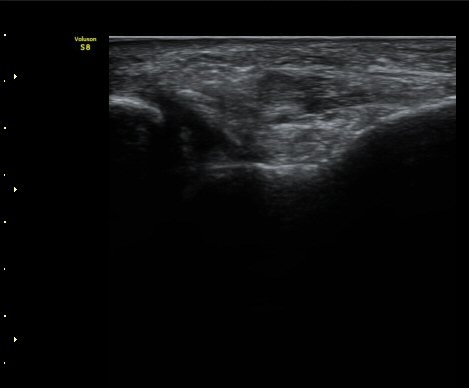

Àü°Å°ñºñ°ñÀδë Á¾´Ü¸é°Ë»ç¿¡¼­ ÀδëÀÇ Àú¿¡ÄÚ ºÎÁ¾ÀÌ °üÂûµÈ´Ù(±×¸² 2).